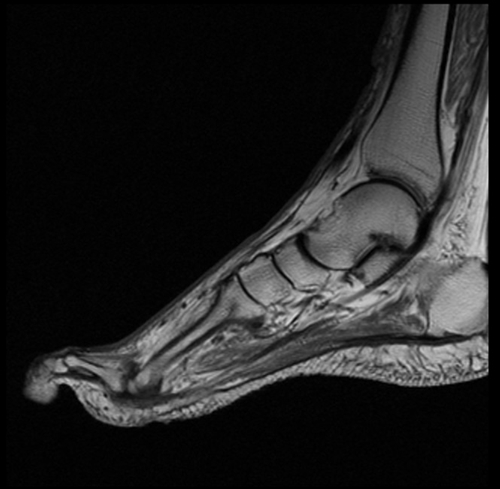

RM sin contraste para pie diabético. Las complicaciones que se pueden producir en el pie durante la evolución de la enfermedad son multifactoriales y a menudo coexisten, dificultando al clínico su diagnóstico diferencial. Un correcto diagnóstico precoz es esencial para establecer el tratamiento adecuado a cada patología.

El enfoque del estudio depende de la sospecha clínica. Cuando no se sospecha infección (osteoartropatía neuropática, artritis aséptica, fracturas) el estudio debe incluir todo el pie.

La complejidad anatómica del pie requiere una localización previa multidireccional que después permita la realización de las diferentes secuencias en los planos ortogonales al área concreta de estudio. Además, dado que son pacientes que suelen requerir de controles sucesivos es necesaria la protocolización de los estudios para que sean similares al inicial y facilitar así la valoración de la evolución de los hallazgos iniciales.

Con respecto a las secuencias a realizar, las secuencias potenciadas en T1 son necesarias para evaluar los cambios en la médula ósea y en el tejido celular subcutáneo. Las secuencias con supresión grasa (STIR) valoran el edema tanto a nivel óseo como en las partes blandas.